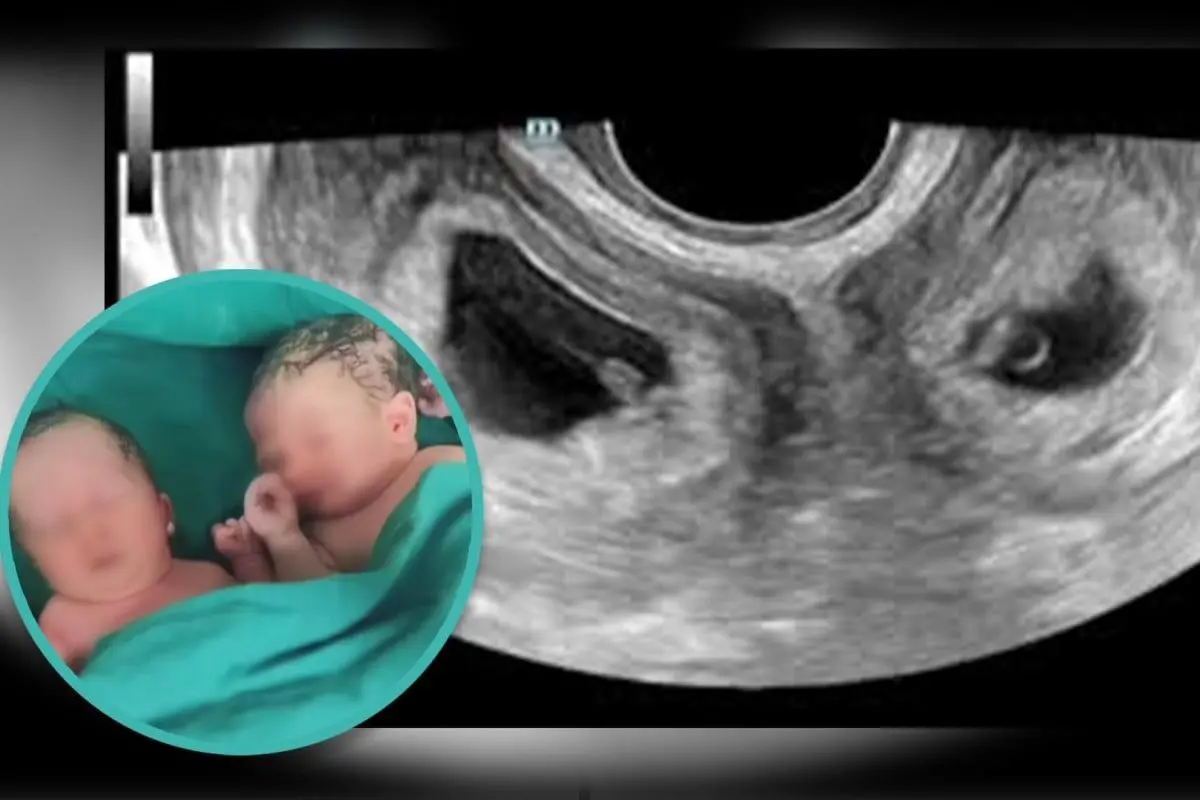

Mulher tem gêmeos em dois úteros diferentes; chance uma em um milhão

Em um caso raríssimo, essa mulher chinesa teve gêmeos vindos de dois úteros diferentes. A condição afeta apenas 0,3% das mulheres no mundo todo. Segundo a Cleveland Clinic, o útero didelfo é uma condição congênita rara em que a mulher nasce com dois úteros.

Ambos os úteros de Li estavam completamente formados e incluíam ovários e ovidutos, segundo a China National Radio. Ela deu à luz a um menino e uma menina, no Hospital Xi’an, na província de Shaanxi, quando estava grávida de oito meses e meio.

Segundo Cai Ying, obstetra sênior do hospital, o caso de Li se aproxima de 1 em 1 milhão.

“Estar grávida em cada um dos dois úteros por concepção natural é muito raro. Ouvimos falar apenas de alguns casos assim, tanto na China quanto no exterior”, explicou.

O garoto pesava 3,3 kg, enquanto a menina veio ao mundo com 2,4 kg.